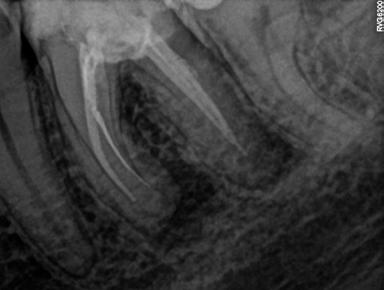

Mind a periapicalis röntgenfelvétel, mind a CBCT-felvétel igazolta, hogy a fragmentum mélyen a gyökércsatorna görbülete mögött, az apikális harmadban helyezkedik el a mesiobuccalis csatornában, valahol a mesiolingualis csatornával történő egyesülés után. Ezenfelül mind a mesialis, mind a distalis gyökércsúcs körül periapicalis gyulladás jelei voltak megfigyelhetőek (1–3. ábra). A betört eszköz nagyjából 5 mm-es hosszúsággal rendelkezett. A mesiolingualis csatornán keresztül a betört fragmentum mellett történő további gyökércsatorna-megmunkálást kockázatosnak ítéltük, mivel nagy esélyt láttunk rá, hogy így a másik eszköz is eltörik, amely pedig a gyökértömés elkészítését nehezítette volna. Azonban a SWEEPS technológiának és a biokerámia sealereknek köszönhetően más megoldási lehetőségek is nyitva álltak előttünk.

ábra: Kiindulási röntgen. A felvételen jól látható a betört eszköz és a periapikális lézió.

2. ábra: Kiindulási CBCT-felvétel. A betört eszköz mélyen a gyökércsatorna görbülete mögött található.

3. ábra: A betört eszköz vége jóval a mesiobuccalis és mesiolinguális csatorna egyesülésének pontja alatt helyezkedik el.